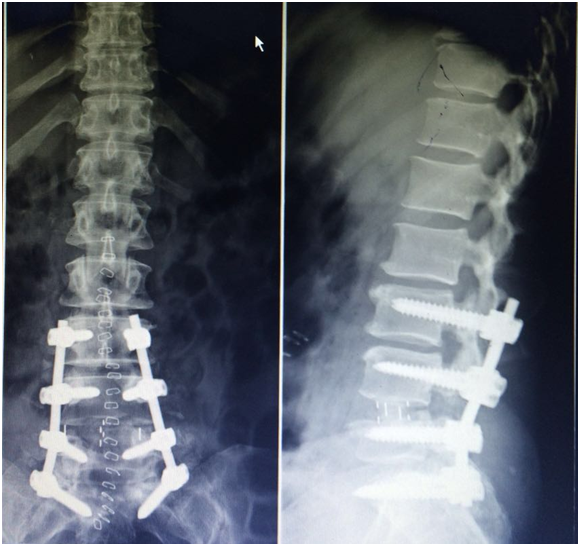

After 3 months, the patient was still complaining of persistent low back pain and inability to ambulate on her lower extremities. All treatment options and possible outcomes were thoroughly discussed with the patient including the poor prognosis regarding the neurological recovery at this point time after the accident. A second operation was done after discussing the the pros and cons and obtaining the consent of the patient. Starting with the posterior approach, Pedicle screws were inserted segmentally from L3 to S1, complete L4-5 facetectomy was done on both sides and both L4 and L5 nerve root were fully decompressed. This was followed by removal of the disc materials from both sides to help in the reduction process, which was achieved using reduction screws at L4 level with special contouring of the rods. Autologous bone graft was applied posetrolaterally. Skin incision was closed and the patient was put in a lateral decubitus position. A cage filled with bone graft was inserted at L4-5 level using the oblique lumbar interbody fusion technique (Figure 3).

Figure 3 A cage filled with bone graft was inserted at L4-5 level using the oblique lumbar interbody fusion technique.